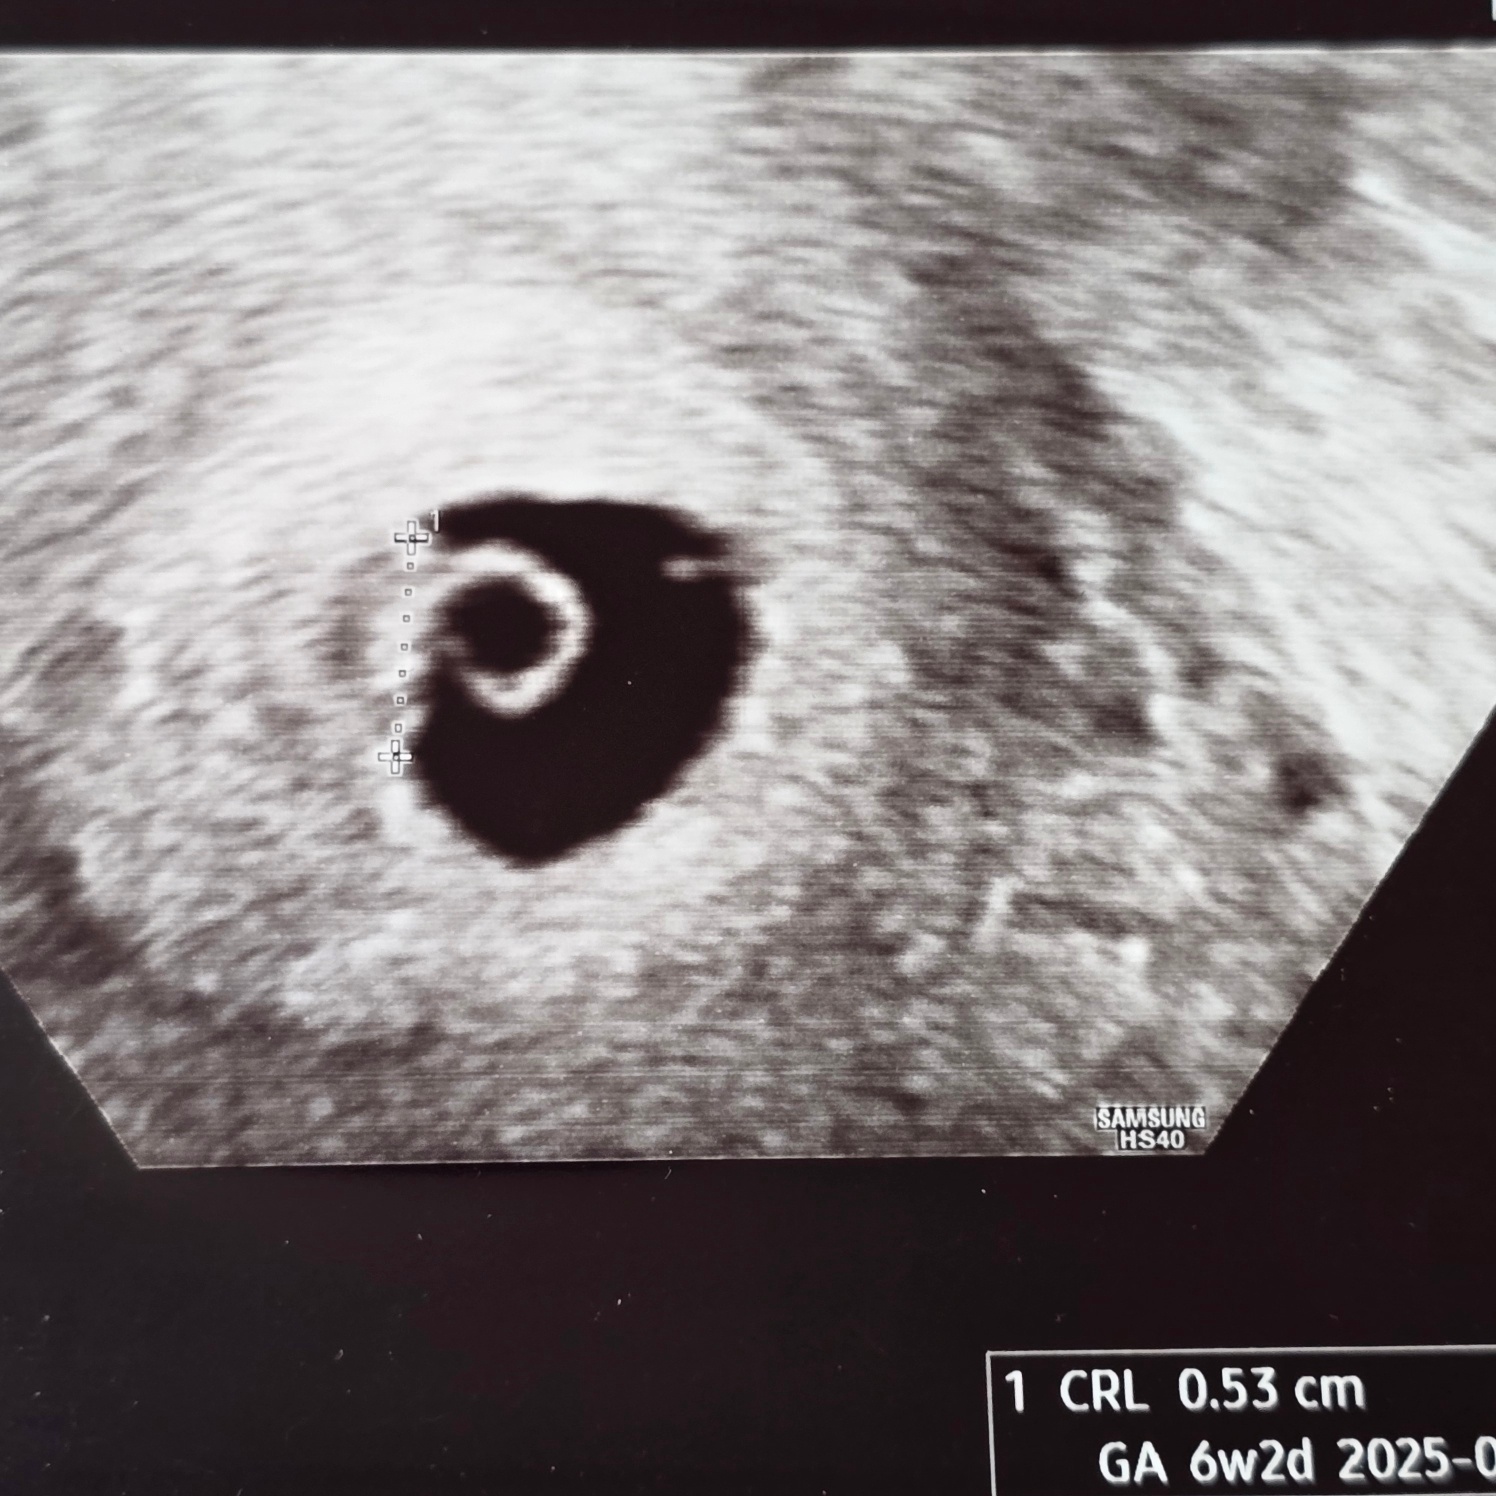

6주 6일 차 - 초음파 확인!

두둥!!!!

커져있는 아기집과 난황!!

그리고 아기 심장소리까지 들었다!!!!

크기는 4일 작지만 따라가기도 하고 착상이 조금 늦었다 생각하면 이대로 유지만 해도 괜찮을 거라고 말씀해 주셨다!!

이대로 쭉 잘 커보자 아가야!!

난황까지 확인하고 나서야 태명을 불러봤다.ㅎㅎ